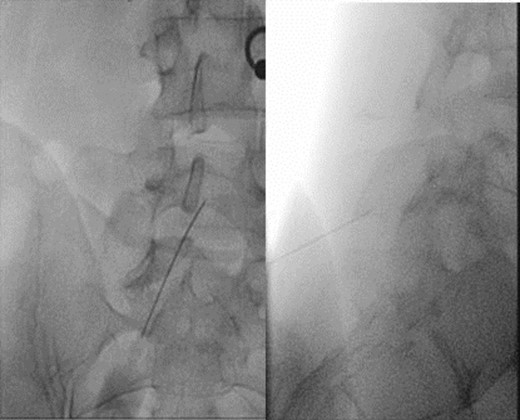

We then repeated the only positive finding we could achieve with a spinous process block at the L4-L5 and L5-S1 levels (Bupivacaine 0.5% + Methylprednisolone), with again an immediate improvement of painful hyperextension. The relief lasted 6 hours as seen on our in–house designed follow-up tool for smartphones questioning in real time every hour for a pain report following diagnostic blocks (Figs 5 and 6). The addition of corticosteroid did not prolong the relief and we therefore proposed, as previously described, to perform a radiofrequency ablation at that level.

Result of the assessment of pain by smartphone application (DolorApp CHUV).